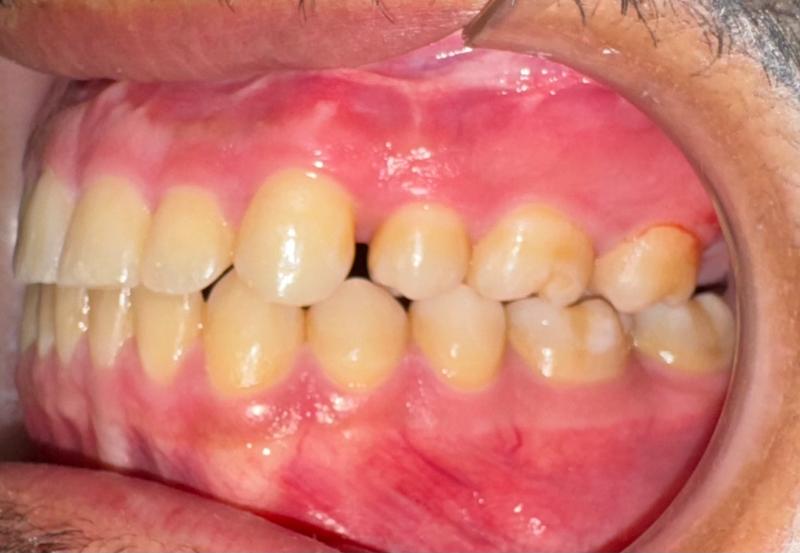

Prima

Il paziente, di 27 anni, si presenta alla mia osservazione già in trattamento ortodontico, a causa di un evidente morso inverso, manifestazione tipica di una terza classe dento-scheletrica.

In collaborazione con il Dott. Laganà e l’ortodontista Di Benedetti, è stato effettuato un attento studio del caso. Si è deciso di completare la fase di decompensazione ortodontica, spiegando al paziente che in questa fase avrebbe assistito ad una temporanea accentuazione del difetto estetico e funzionale, necessaria per garantire il successo della fase chirurgica.